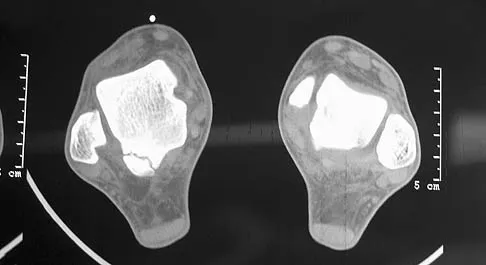

Figure 7 shows the CT scan of a 25-year-old soccer player who has had posterior ankle pain with plantar flexion for the past 2 years. Immobilization has failed to provide relief. He is ambulatory. Management should consist of

Explanation